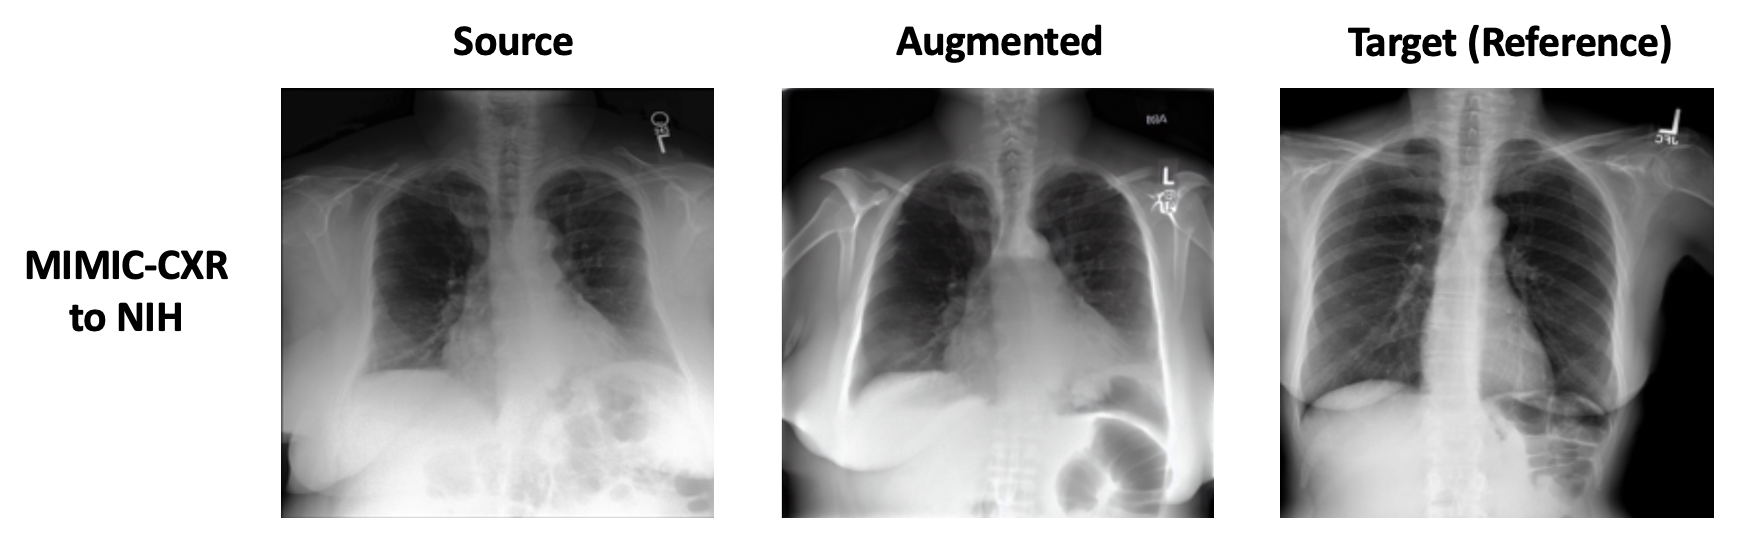

5.2 Generalizing Dataset Shifts in Chest X-ray Images

We evaluate global shifts in a medical setting with a transfer between Chest X-ray datasets. With a transfer from MIMIC-CXR to NIH ChestXray14, we see from Table 1 that MaskedMedPaint has the best generalization to target domain (AUROC 0.546) with LADS being a close second (AUROC 0.521). All methods except Masked perform with higher than AUROC 0.7 in the source domain. Qualitatively, we see that artifacts such as radiology markers and general image contrast can differ in the generated augmentations (Figure 3).